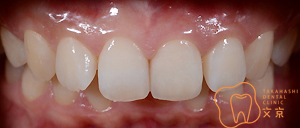

■前歯を治したい。 オールセラミックスによる審美治療

■前歯を治したい。40代男性 オールセラミックスによる審美治療

■前歯を治したい 精密審美治療・セラミックス治療

■前歯 精密審美治療

■前歯のセラミックス治療 審美治療

■前歯のオールセラミックス治療